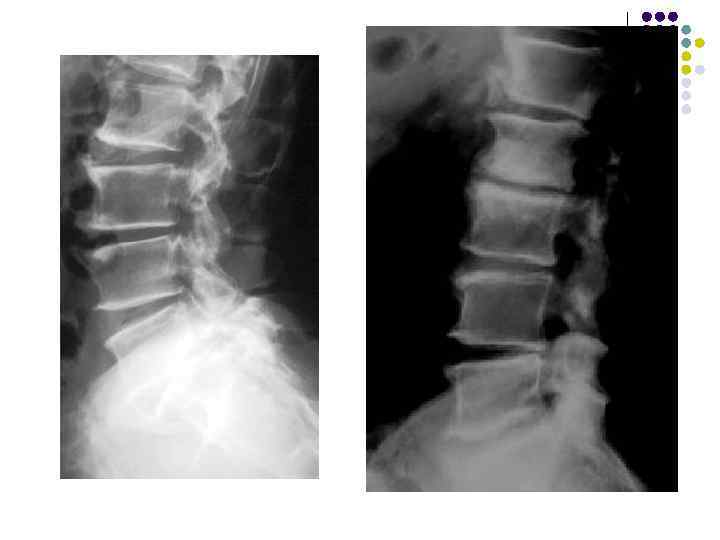

l l l На рентгенограмме шейного отдела позвоночного столба в боковой проекции определяется: выраженные распространенные дистрофические изменения в виде остеохондроза и артроза дугоотростчатых суставов: неравномерное сужение межпозвонковых пространств, субхондральный остеосклероз, костные разрастания по краям тел позвонков, сужение рентгеновских суставных щелей дугоотостчатых суставов с субхондральным остеосклерозом и небольшими костными разрастаниями по краям суставных поверхностей. Наиболее ярко эти изменения выражены в сегментах С 5 -6 -7 Признаки ограниченного смещения тел позвонков в виде симптома «распорки» и кифотической установки. Заключение: Остеохондроз шейного отдела позвоночного столба. Артроз дугоотростчатых суставов. Деформация шейного отдела позвоночника с нарушением статики.

1.

l l l На рентгенограмме шейного отдела позвоночного столба в боковой проекции определяется: выраженные дистрофические изменения за счет остеохондроза - значительное, неравномерное сужение межпозвонковых пространств с нарушением их правильной клиновидной формы, выраженный субхондральный остеосклероз, значительные костные разрастания по передним краям тел позвонков. Наиболее ярко эти изменения представлены в сегментах С-5, 6, 7. Помимо этого, в этих же сегментах фиксируются дистрофические изменения дугоотростчатых суставов – сужение рентгеновских суставных щелей, субхондральный остеосклероз и костные разрастания по краям суставных поверхностей. Выпрямление физиологического лордоза. Признаки системного нарушения статики тел позвонков в виде симптомов кифотической установки. Деструктивных изменений нет Заключение: Комплекс дистрофических изменений шейного отдела позвоночного столба в виде остеохондроза и артроза дугоотростчатых суставов с преимущественными проявлениями в нижних сегментах отдела. Нарушение статики тел позвонков

3.

l На рентгенограмме шейного отдела позвоночного столба в боковой проекции определяется: выраженные дистрофические изменения за счет остеохондроза с преимущественными проявлениями в сегменте С 5 -6 – сужение и деформация межпозвонковых пространств, выраженный субхондральный остеосклероз, значительные костные разрастания по краям тел позвонков. Выпрямление физиологического лордоза. Признаки нарушения положения тела С 4 (симптом «распорки» )

l На рентгенограммах шейного отдела позвоночного столба в двух проекциях определяется комплекс выраженных дистрофических изменений с преимущественными проявлениями в сегментах С 5 -6 -7 в виде остеохондроза и выраженного спондилоза за счет неравномерного сужения межпозвонковых пространств, субхондрального отсеосклероза и костных разрастаний как по краям тел позвонков с продолжением плоскости замыкательной площадки, так и под передней продольной связкой с образованием мощного костного соединения. Положение тел позвонков правильное, деструктивных изменений нет.